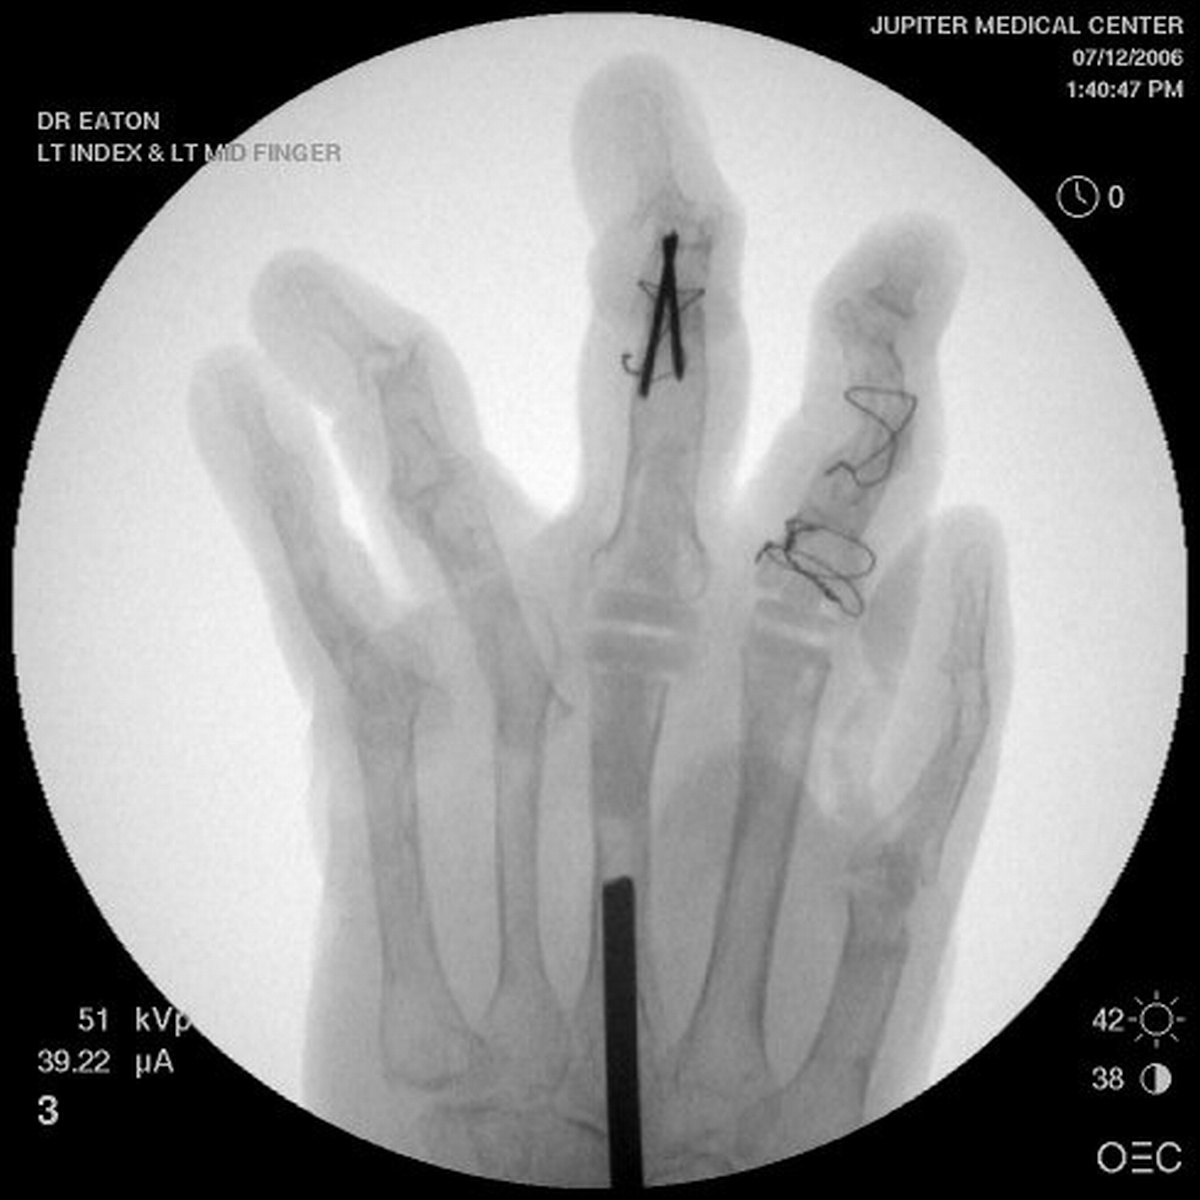

Clinical Example: Rheumatoid reconstruction with metacarpal head bone graft to recreate proximal phalanx dorsal cortex for silastic MCP arthroplasty

Rheumatoid arthritis commonly affects the hands in a variety of ways. Although more effective medications have lessened the number of patients requiring reconstruction for rheumatoid hand deformities, surgery is needed for some cases. This case demonstrates MCP arthroplasty using bone graft from the metacarpal head to recreate the dorsal cortex of the proximal phalanx lost from chronic subluxation.

Xrays show radiocarpal collapse, proximal migration of the proximal phalanges, flail PIP joints and loss of the proximal half of the dorsal cortex of the proximal phalanges.

Below are xrays after the first set of reconstructions.